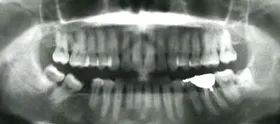

奥歯を1本長期間失ったケース

■治療前

向かって左の下の奥歯が、長期間失ったまま放置されていました。その為、向かって左奥の2本の歯が、前に倒れるように傾いてしまっていました。

まず、この傾きを治しました。治療期間は4ヶ月です。

■治療中

■治療後

■治療中レントゲン写真

その後、歯を失った場所には、人工の歯根であるインプラントを埋めて、白い歯をかぶせました。

■治療後レントゲン写真

このようにして、従来なら前と後ろの歯を削って治していくブリッジにせずに、治すことができました。

| 主訴 | 右下の奥歯をずいぶん前に抜きそのままにしていたら、奥歯が倒れてきた |

| 治療方法 | 部分矯正治療+インプラント治療 |

| 治療期間 | 約10か月 |

| 通院回数等 | 12回位 |

| 費用 | 約80万円 |

| リスク・副作用 | インプラント術後の腫れ・痛み |